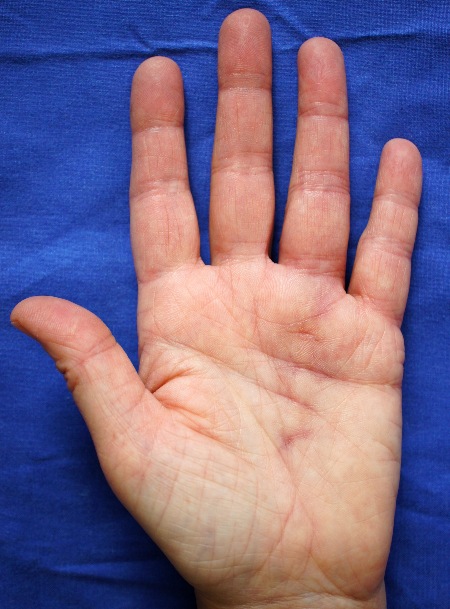

Berührungsfreie Temperaturmessung der Hand bei M. Sudeck (CRPS Typ 1) Hier Stadium 1.

Berührungsfreie Temperaturmessung der Hand bei M. Sudeck (CRPS Typ 1) Hier Stadium 1.